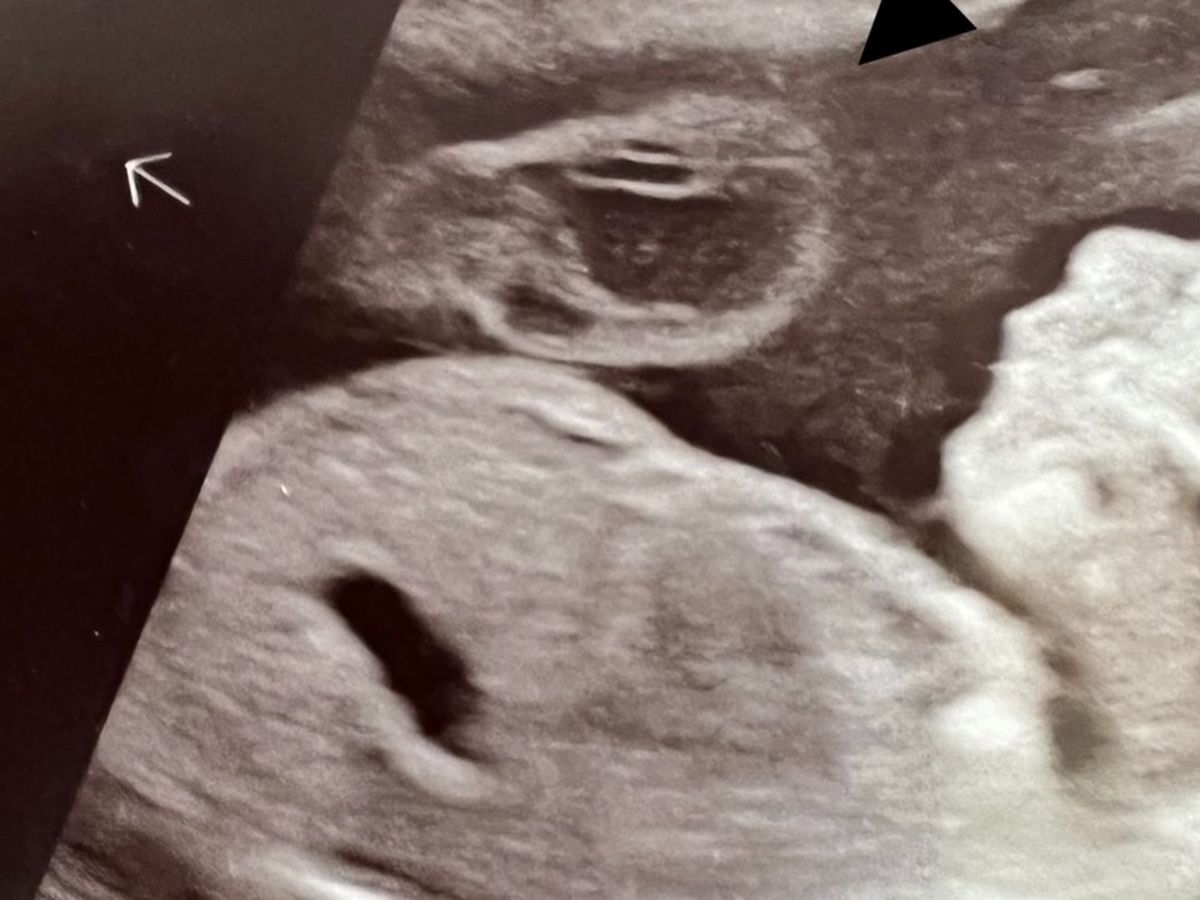

Please help my close friend, Isabella, and her family, with this necessary life saving surgery for her unborn baby and herself. She is in her third trimester, and her baby was diagnosed with omphalocele. This is when the organs are growing outside of the baby's belly. Fortunately it is only baby Luca's intestines. The doctors say it is a small surgery and are very positive! Of course we know it's essential for his survival!

On top of that, the mother has placenta accreta. So the doctors are preparing a C section plan a month before her due date to be prepared for whatever may happen during surgery, to save Isabella's life, if necessary. Placenta accreta is when the placenta is embedded into the uterine wall. So the risk is uncontrollable bleeding. They may have to remove her uterus completely to save her life.